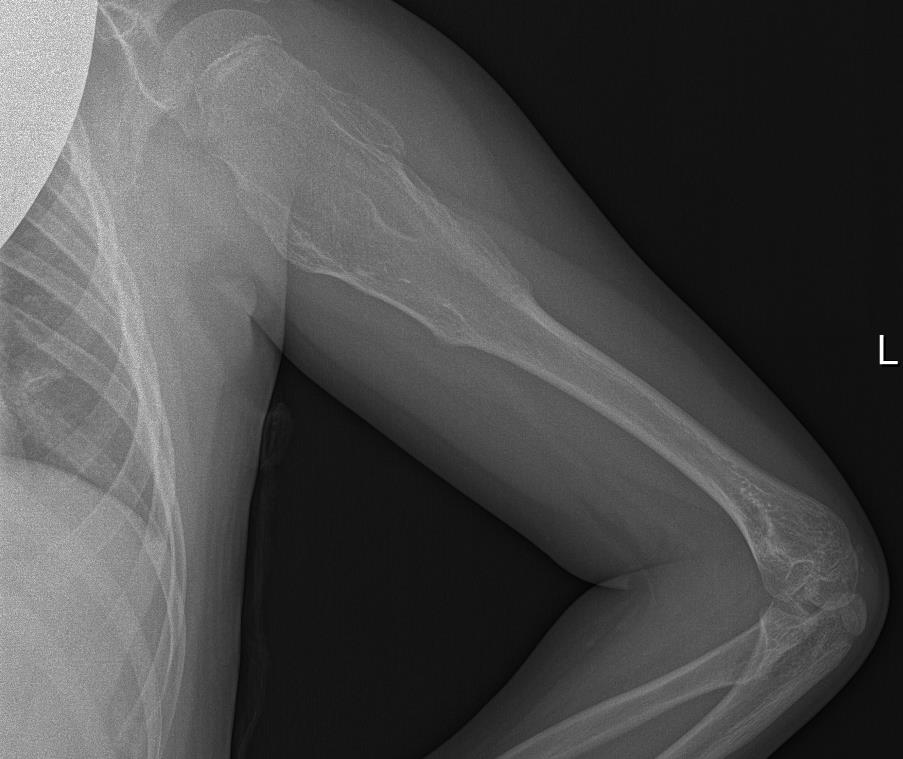

Radiografía de Miembro superior izquierdo: Se visualiza lesión lítica metafiso-diafisaria en húmero izquierdo expansiva con excrecencias óseas y margen estrecho con hueso sano.